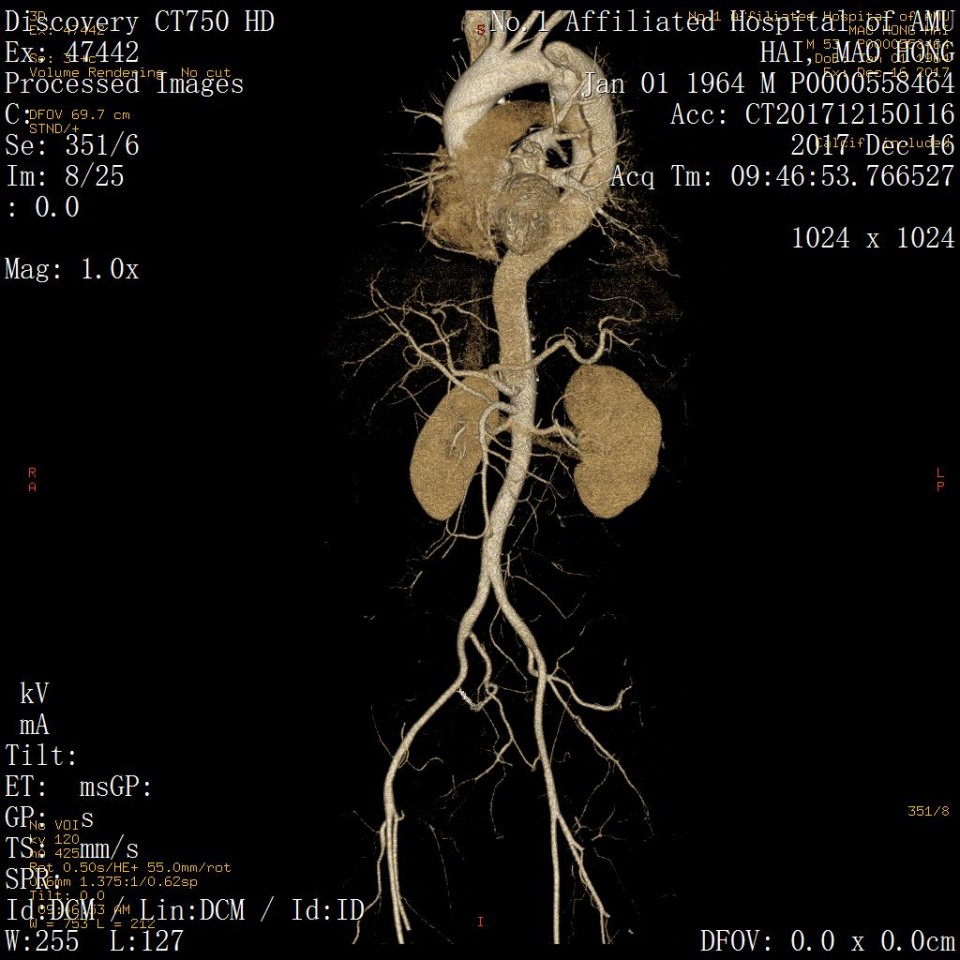

近日,我院血管外科成功应用Castor分支型支架(图1)治疗胸主动脉夹层一例,该病例为我省的首例植入。患者男性,53岁,因“突发胸痛2天”入院,既往有高血压病史。经CTA检查诊断为胸主动脉夹层,破口距离左锁骨下动脉(LSA)36mm,假腔逆撕至左锁LSA(图2、3)。既往一般选用直管型支架,需要部分或全部封闭LSA,但可能增加脑梗和截瘫风险。考虑到患者年龄较轻又是体力劳动者,经科室讨论决定使用Castor一体式分支型覆膜支架,一方面通过增加健康锚定区 (LCCA-LSA距离+LSA直径),进一步降低支架对于血管壁的刺激,从而降低夹层逆撕的风险;另一方面重建LSA保留功能,且不影响LCCA血流。 整个手术过程顺利,最后造影:Castor分支型支架定位精准,无移位;支架近端三重小波段密封性能良好,无内漏,破口被完全封堵,真腔被打开;LSA及LCCA血流通畅,手术圆满成功。病人术后恢复良好(图4、5、6)。